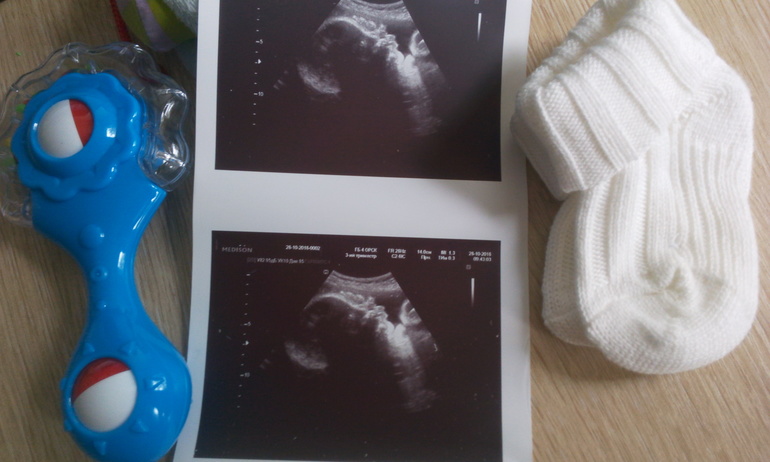

А вот и третий скрининг!

Это УЗИ пойдет как третий скрининг уже.

Всё хо-ро-шо с малышом! Красивый!

Весит мой мальчик приблизительно 1500 грамм. Есть факторы, которые могут немножко искажать расчет параметров. Но! через две недели контроль- так что еще уточним.

Наконец-то мне вручили фото моего мальчика. Первое фото- когда я шла только уточнять что там с плодным яйцом и где оно (на фотке просто пипка со светлым пятнышком сердечка), а тут... вот вам и лобик, и носик курносый и причмокивающие губки.

Вообще в этот раз он закрывал ладошками личико, и доктор его слегка подтолкнул- тот ладошки сдвинул в стороны и мы успели сделать фото, прежде чем малыш отвернулся совсем (спать ребенку не дают, ага).